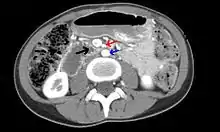

Abdominal and pelvic computed tomography scan showing duodenal compression (black arrow) by the superior mesenteric artery (red arrow) and the abdominal aorta (blue arrow).

Diagnosis is very difficult, and usually one of exclusion. SMA syndrome is thus considered only after patients have undergone an extensive evaluation of their gastrointestinal tract including upper endoscopy, and evaluation for various malabsorptive, ulcerative and inflammatory intestinal conditions with a higher diagnostic frequency. Diagnosis may follow X-ray examination revealing duodenal dilation followed by abrupt constriction proximal to the overlying SMA, as well as a delay in transit of four to six hours through the gastroduodenal region. Standard diagnostic exams include abdominal and pelvic computed tomography (CT) scan with oral and IV contrast, upper gastrointestinal series (UGI), and, for equivocal cases, hypotonic duodenography. In addition, vascular imaging studies such as ultrasound and contrast angiography may be used to indicate increased bloodflow velocity through the SMA or a narrowed SMA angle.[14][15]